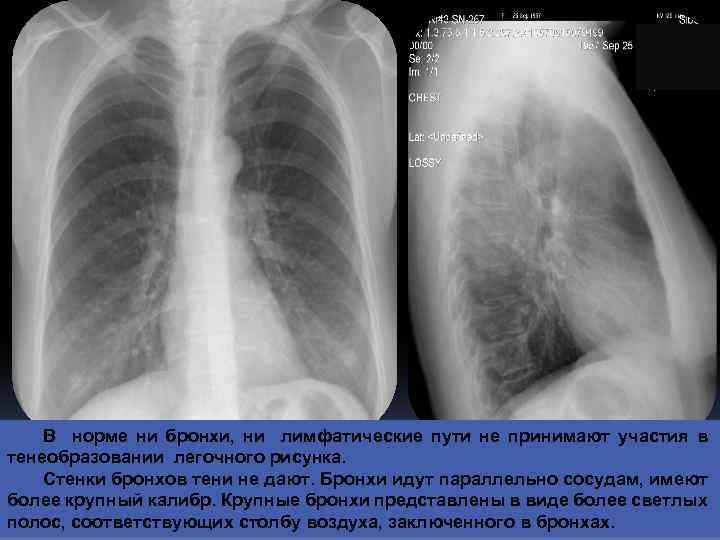

В норме ни бронхи, ни лимфатические пути не принимают участия в тенеобразовании легочного рисунка. Стенки бронхов тени не дают. Бронхи идут параллельно сосудам, имеют более крупный калибр. Крупные бронхи представлены в виде более светлых полос, соответствующих столбу воздуха, заключенного в бронхах.